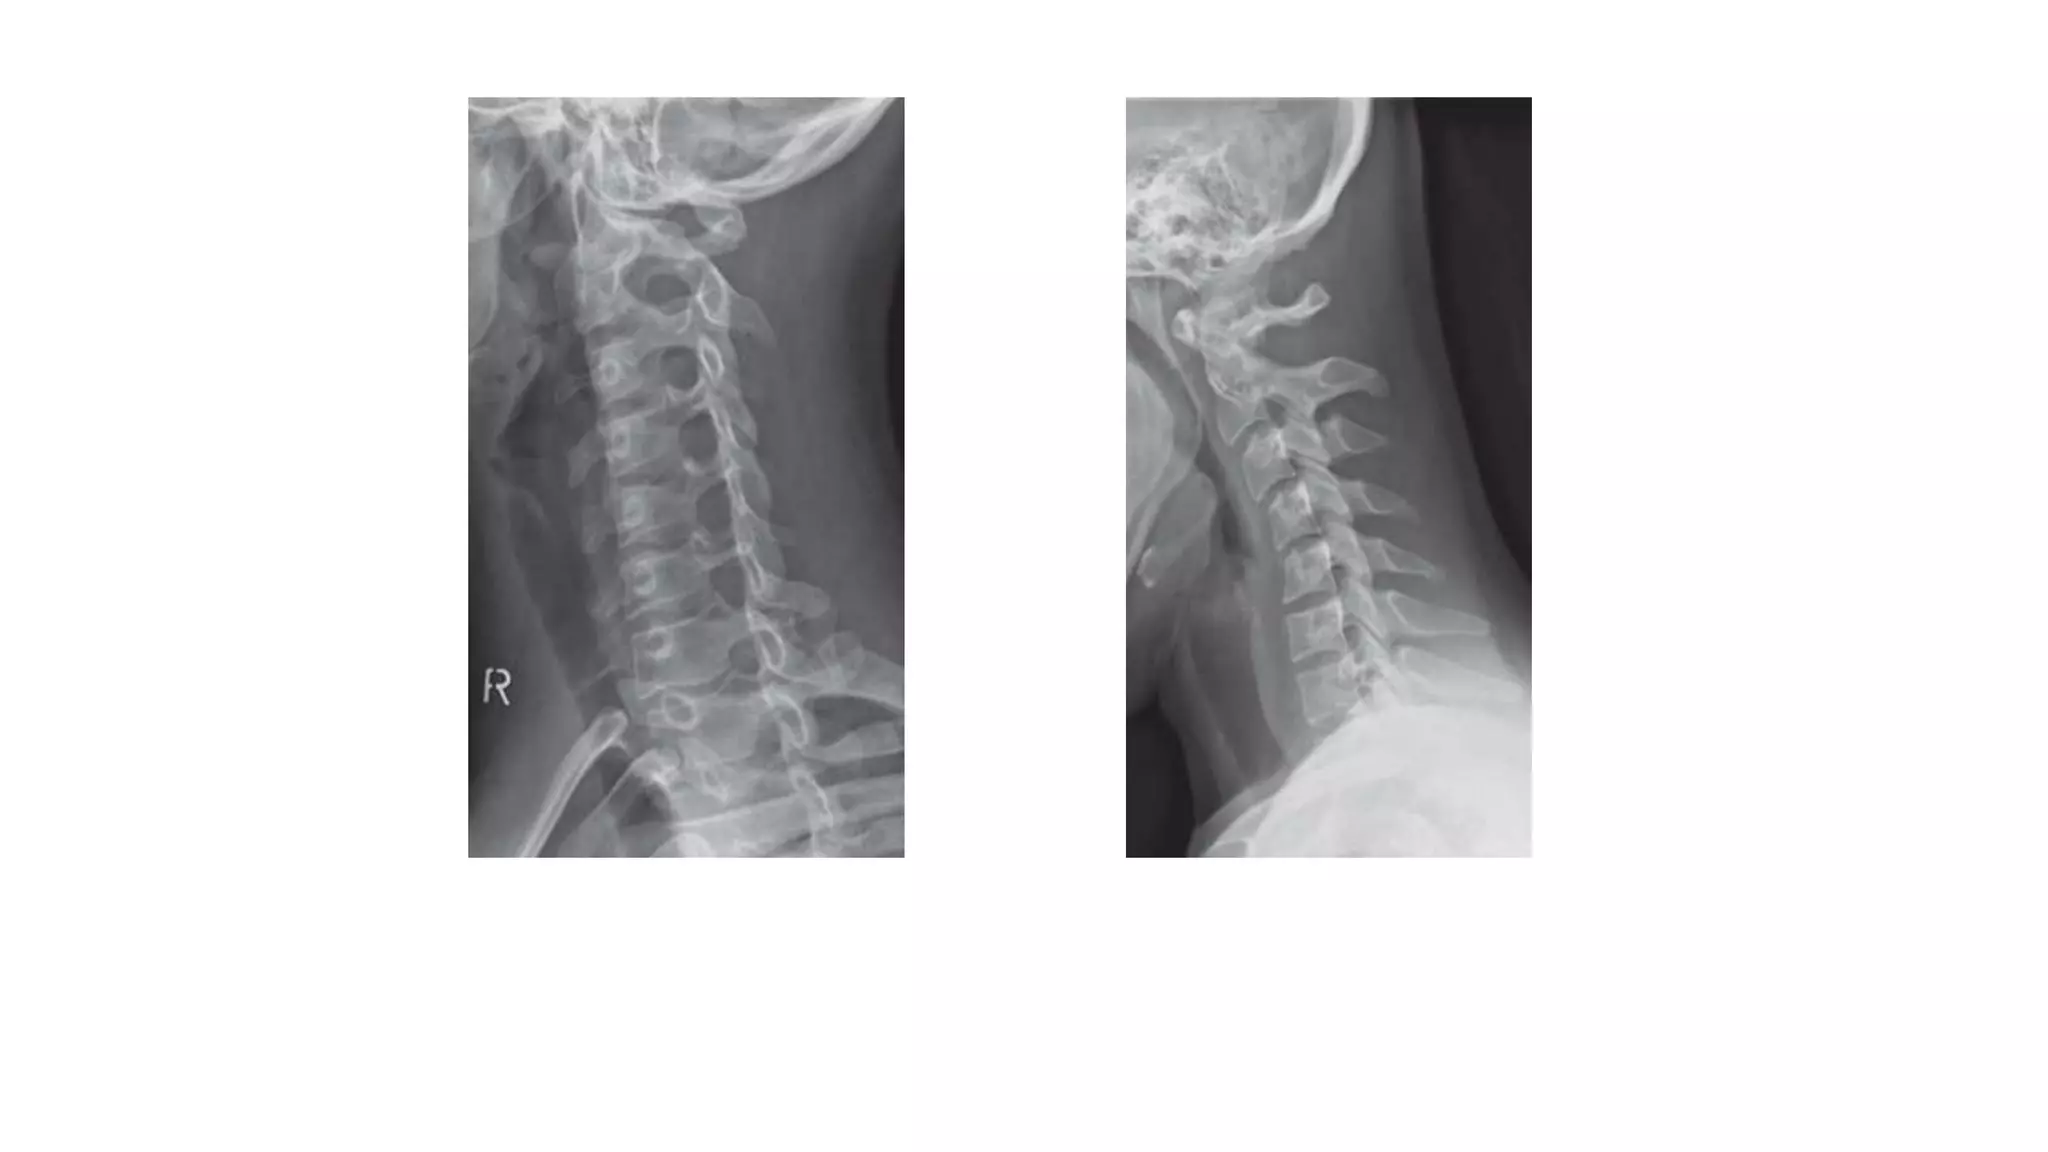

Normal plain radiography of the cervical spine

ANTERIOR POSTERIOR

VIEW

LATERAL VIEW

Right oblique view Dynamic flexion view

• Normal cervicalspine. • Five lines • A : the anterior longitudinal line • P: Posterior longitudinal line. • These run along the margin of the anterior and posterior longitudinal ligament. • L is the spinolaminar line, which runs between the anterior margin of the dorsal spines, outlining the posterior margin of the spinal canal. • The asterisks represent the spinous line, along the posterior margin of the dorsal spines. • F is the posterior pillar line, along the posterior margins of the articular pillars

• 44.

Normal plain radiographyof the cervical spine ANTERIOR POSTERIOR VIEW LATERAL VIEW

• 45.

Right oblique viewDynamic flexion view